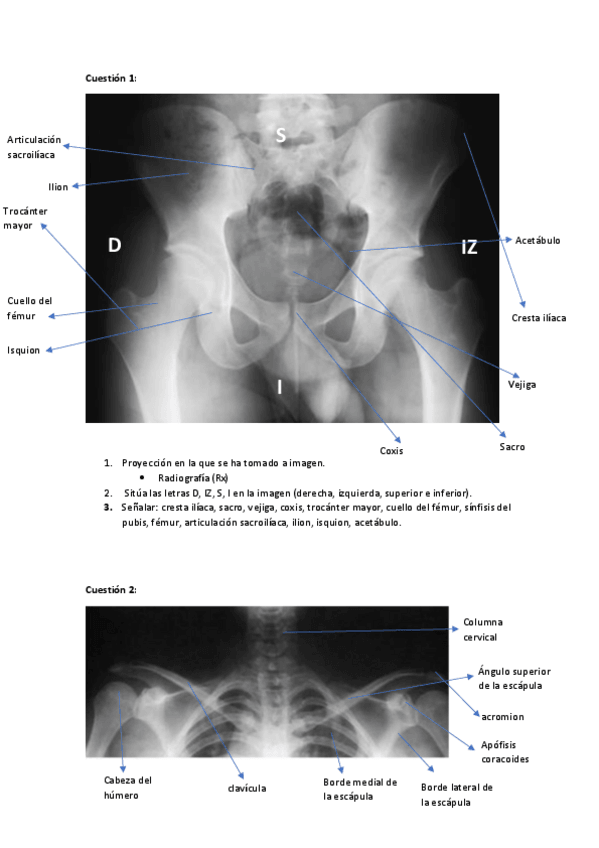

Prácticas laboratorios anatomía

He publicado nuevos apuntes de 1º Anatomía Humana: Prácticas laboratorios anatomía

practicas-anatomia-act-4.pdf

actividad-5-y-6-anatomia.pdf

Anatomia-palpatoria.pdf

Practicas-anatomia-actividad-3.pdf